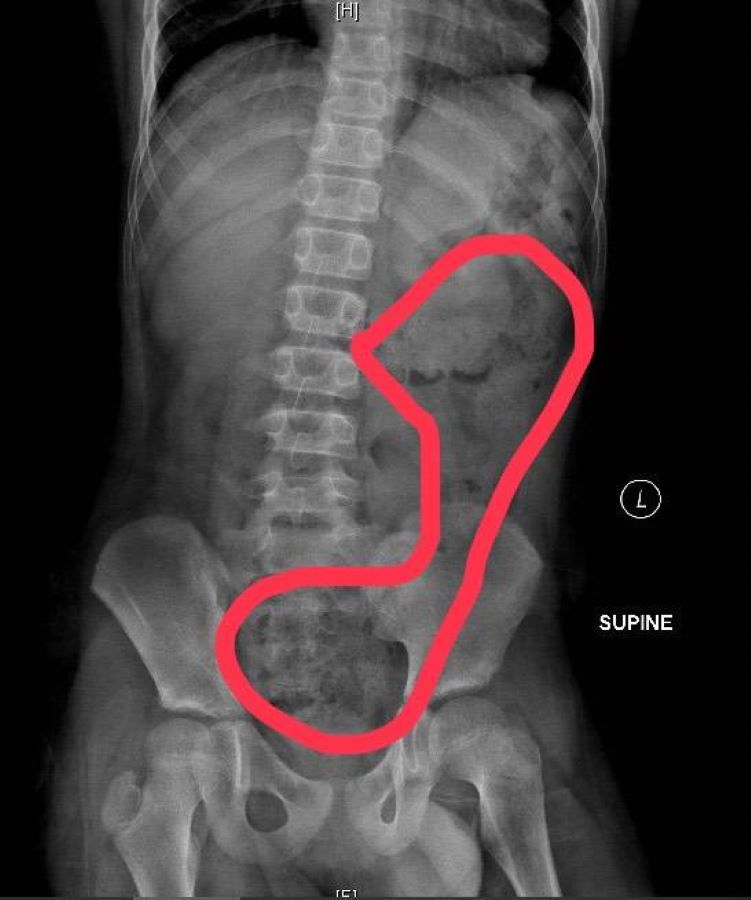

另一名6歲女孩除了肚子痛得直哭叫,腹部並明顯異常脹大,經腹部X光檢查發現她"一肚子大便"!媽媽說她可能剛上小學,還沒習慣上課節奏,有便意也忍著不去廁所,就連幾天沒上大號也記不清,直到症狀嚴重掛急診。

▲6歲女生X光片,畫圈部分為積糞。